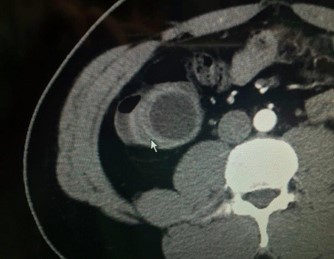

Figure 2: TC appearance of appendiceal neoplasm (arrow).

Appendiceal mucinous neoplasm accounts for 8-10% of appendiceal tumors and nearly 58% of malignant appendiceal tumors. LAMN is a borderline or low-grade malignant tumor, regardless of rupture, and is characterized by implantation metastasis [2-4]. Its pathogenesis involves atypical hyperplasia of the glandular appendix epithelium that obstructs the appendix with a gradual accumulation of mucus resulting in increased pressure. Mucus penetrates the muscularis mucosa and produces mucinous masses around the appendix and in the retroperitoneum [9-12]. Most cases are asymptomatic, and in the absence of acute infection, the symptoms and signs of LAMN resemble those of chronic appendicitis [13]. In our series, we observed and grouped the cases as patients treated only with appendectomy (5 patients) and as patients treated with cecal resection or Right Hemicolectomy (RH) (13 patients). It is important to underline that, in our experience, some patients underwent more extensive surgery for advanced disease. In fact, we performed surgery with peritoneal cytoreduction and Hipec in 7 cases. As other Authors reported in their analysis, we had similar data at pathology specimen as median size of primary tumour was 4.5 cm and surgical margins after colonic resection were free of tumor in all cases. A correct diagnosis of appendiceal neoplasm may be difficult, but on physical examination large tumors can be found as a complete oval mass with no surrounding adhesions [10]. An appendiceal mucinous cyst that forms from an appendiceal lesion can easily be misdiagnosed as a common appendiceal abscess or right adnexal cyst. In terms of resectability criteria for appendiceal mucoceles, the decision to perform an appendectomy versus a more extensive procedure, such as right hemicolectomy, is guided by several key factors [14-16,21]. Studies have shown that tumors confined to the distal appendix without cecal involvement can be managed with a simple appendectomy, while those extending to the appendiceal base or demonstrating high-grade features require a cecal resection or right hemicolectomy to achieve clear margins and reduce recurrence [5,16]. Additional evidence indicates that involvement of the mesoappendix or adjacent structures increases the risk of mucin spillage and subsequent pseudomyxoma peritonei, warranting more aggressive surgical intervention [6,11,20]. These criteria, along with tumor size and the possibility of lymphatic spread, although rare in lowgrade lesions, are central to intraoperative decision-making. In the study of Rauwerdink et al. [13] it is observed that AMN histology does not always reflects its associated PMP grade, while PMP grade strongly influences survival. By carefully assessing these factors, surgeons can determine the most appropriate extent of resection and thereby optimize patient outcomes. Abdominal ultrasound and CT or MRI are auxiliary diagnostic methods that can distinguish appendiceal mucinous cysts from other lesions before surgery [18,19]. CT is a more accurate imaging method for the diagnosis of appendiceal neoplasms, and shows a cystic mass closely adjacent to the cecum, with a round or long tubular shape, thin wall, and a smooth and regular outline. When CT shows an irregular cyst wall and thick soft tissue, it is more likely to be malignant. MRI performed with a variety of sequences and scanning methods, and high tissue resolution can clearly and consistently distinguish the wall and fluid of the appendiceal mucinous cyst, and more accurately show the integrity and boundary of the cyst wall. In this case, additional MRI evaluation showed typical manifestations of appendiceal cysts [16,19]. Recently in a clinical study, Guaglio et al. [5] observed that if LAMN had been radically resected with appendectomy, even with limited peritoneal spread, it recurred unlikely; furthermore, appendix wall perforation and the presence of mucin, cells, or both outside the appendix did not carry a higher risk of metachronous peritoneal dissemination. Moreover, in the study of Young et al. [6] were analyzed patients with positive surgical margin or perforated neoplasm with mucin on the serosal surface of the appendix, but right hemicolectomy seemed to offer no additional benefit over appendectomy alone. However, Wang et al. [11] operated 159 patients with LAMN and, after a median follow-up time of 38 months, observed that 7 patients recurred and developed pseudomyxoma peritonei. These Authors stated that surgery plus Hipec was necessary for LAMN after complete removal in patients with a high risk of recurrence. At the same, Gibson et al. [3] studied 223 patients with pseudomyxoma peritonei and stated that survival was more closely associated with the grade of the peritoneal disease than with the grade of the primary neoplasm. Their findings support the developing concept that mutational analysis may provide prognostic information in patients with PMP. But, when mucin is found intraoperatively, surgeons should consider appendectomy with possible conversion to an open approach for thorough exploration. Emergency HIPEC is unnecessary during appendectomy; instead, it should be planned electively after resolution of the acute clinical situation and with the definitive histological examination. It is important to underline that in a recent study of Salminen et al. [10] the appendiceal tumor rate in patients with periappendicular abscess was 14.3%, which was higher compared with uncomplicated acute appendicitis (14.3% vs 1.5%) and complicated acute appendicitis without periappendicular abscess (14.3% vs 2.4%). Of these 54 tumors, there were 21 low-grade appendiceal mucinous neoplasms, 20 adenocarcinomas, 8 adenomas, and 5 neuroendocrine tumors. The factors contributing to the development of PMP from appendiceal neoplasm remain unclear. However, based on the results of the most recent analysis, patients with mucin on mesoappendix or neoplastic epithelium extending into muscularis propria/serosa, perforation and positive margin have a higher risk of developing into PMP [11]. Therefore, the majority of the surgeons suggested and performed cytoreduction plus Hipec on these patients.